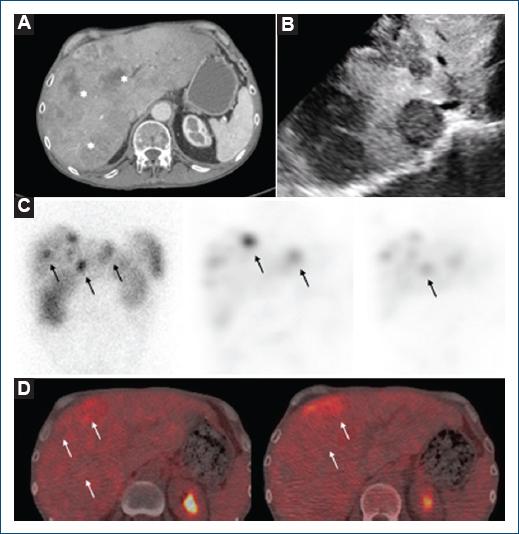

We present a 60-year-old man with an 11-year history of an ileocecal neuroendocrine tumor (NET) with a 1% proliferation index (Ki-67) and carcinoid syndrome (CS) as the first clinical manifestation. Liver metastases were documented by computed tomography and abdominal ultrasound (Figs. 1A and B), with somatostatin receptor expression demonstrated by scintigraphy (Fig. 1C). Positron emission tomography and computed tomography revealed a discrete heterogeneous pathological increase in metastasis metabolism (Fig. 1D). As an initial treatment, surgical resection of the tumor was performed, and somatostatin analogs started. After 11 years, liver metastases and CS persisted despite fifth-line oncologic treatment. During follow-up, echocardiograms were performed periodically, the last two years earlier.

Figure 1 Multimodal imaging metastases. A: computed tomography highlights multiple liver lesions predominantly in the right lobe, with solid aspect and partially confluent that is compatible with liver metastases (asterisks). B: abdominal ultrasound with heterogeneous liver and multiple solid focal lesions. C: scintigraphy reveals multiple active focal deposits of In-111 octreotide in the liver, suggesting the expression of somatostatin receptors in liver metastases (arrows). D: axial positron emission tomography/computed tomography shows most liver metastases without increased metabolism and heterogeneously low 18F-FDG uptake (arrows).